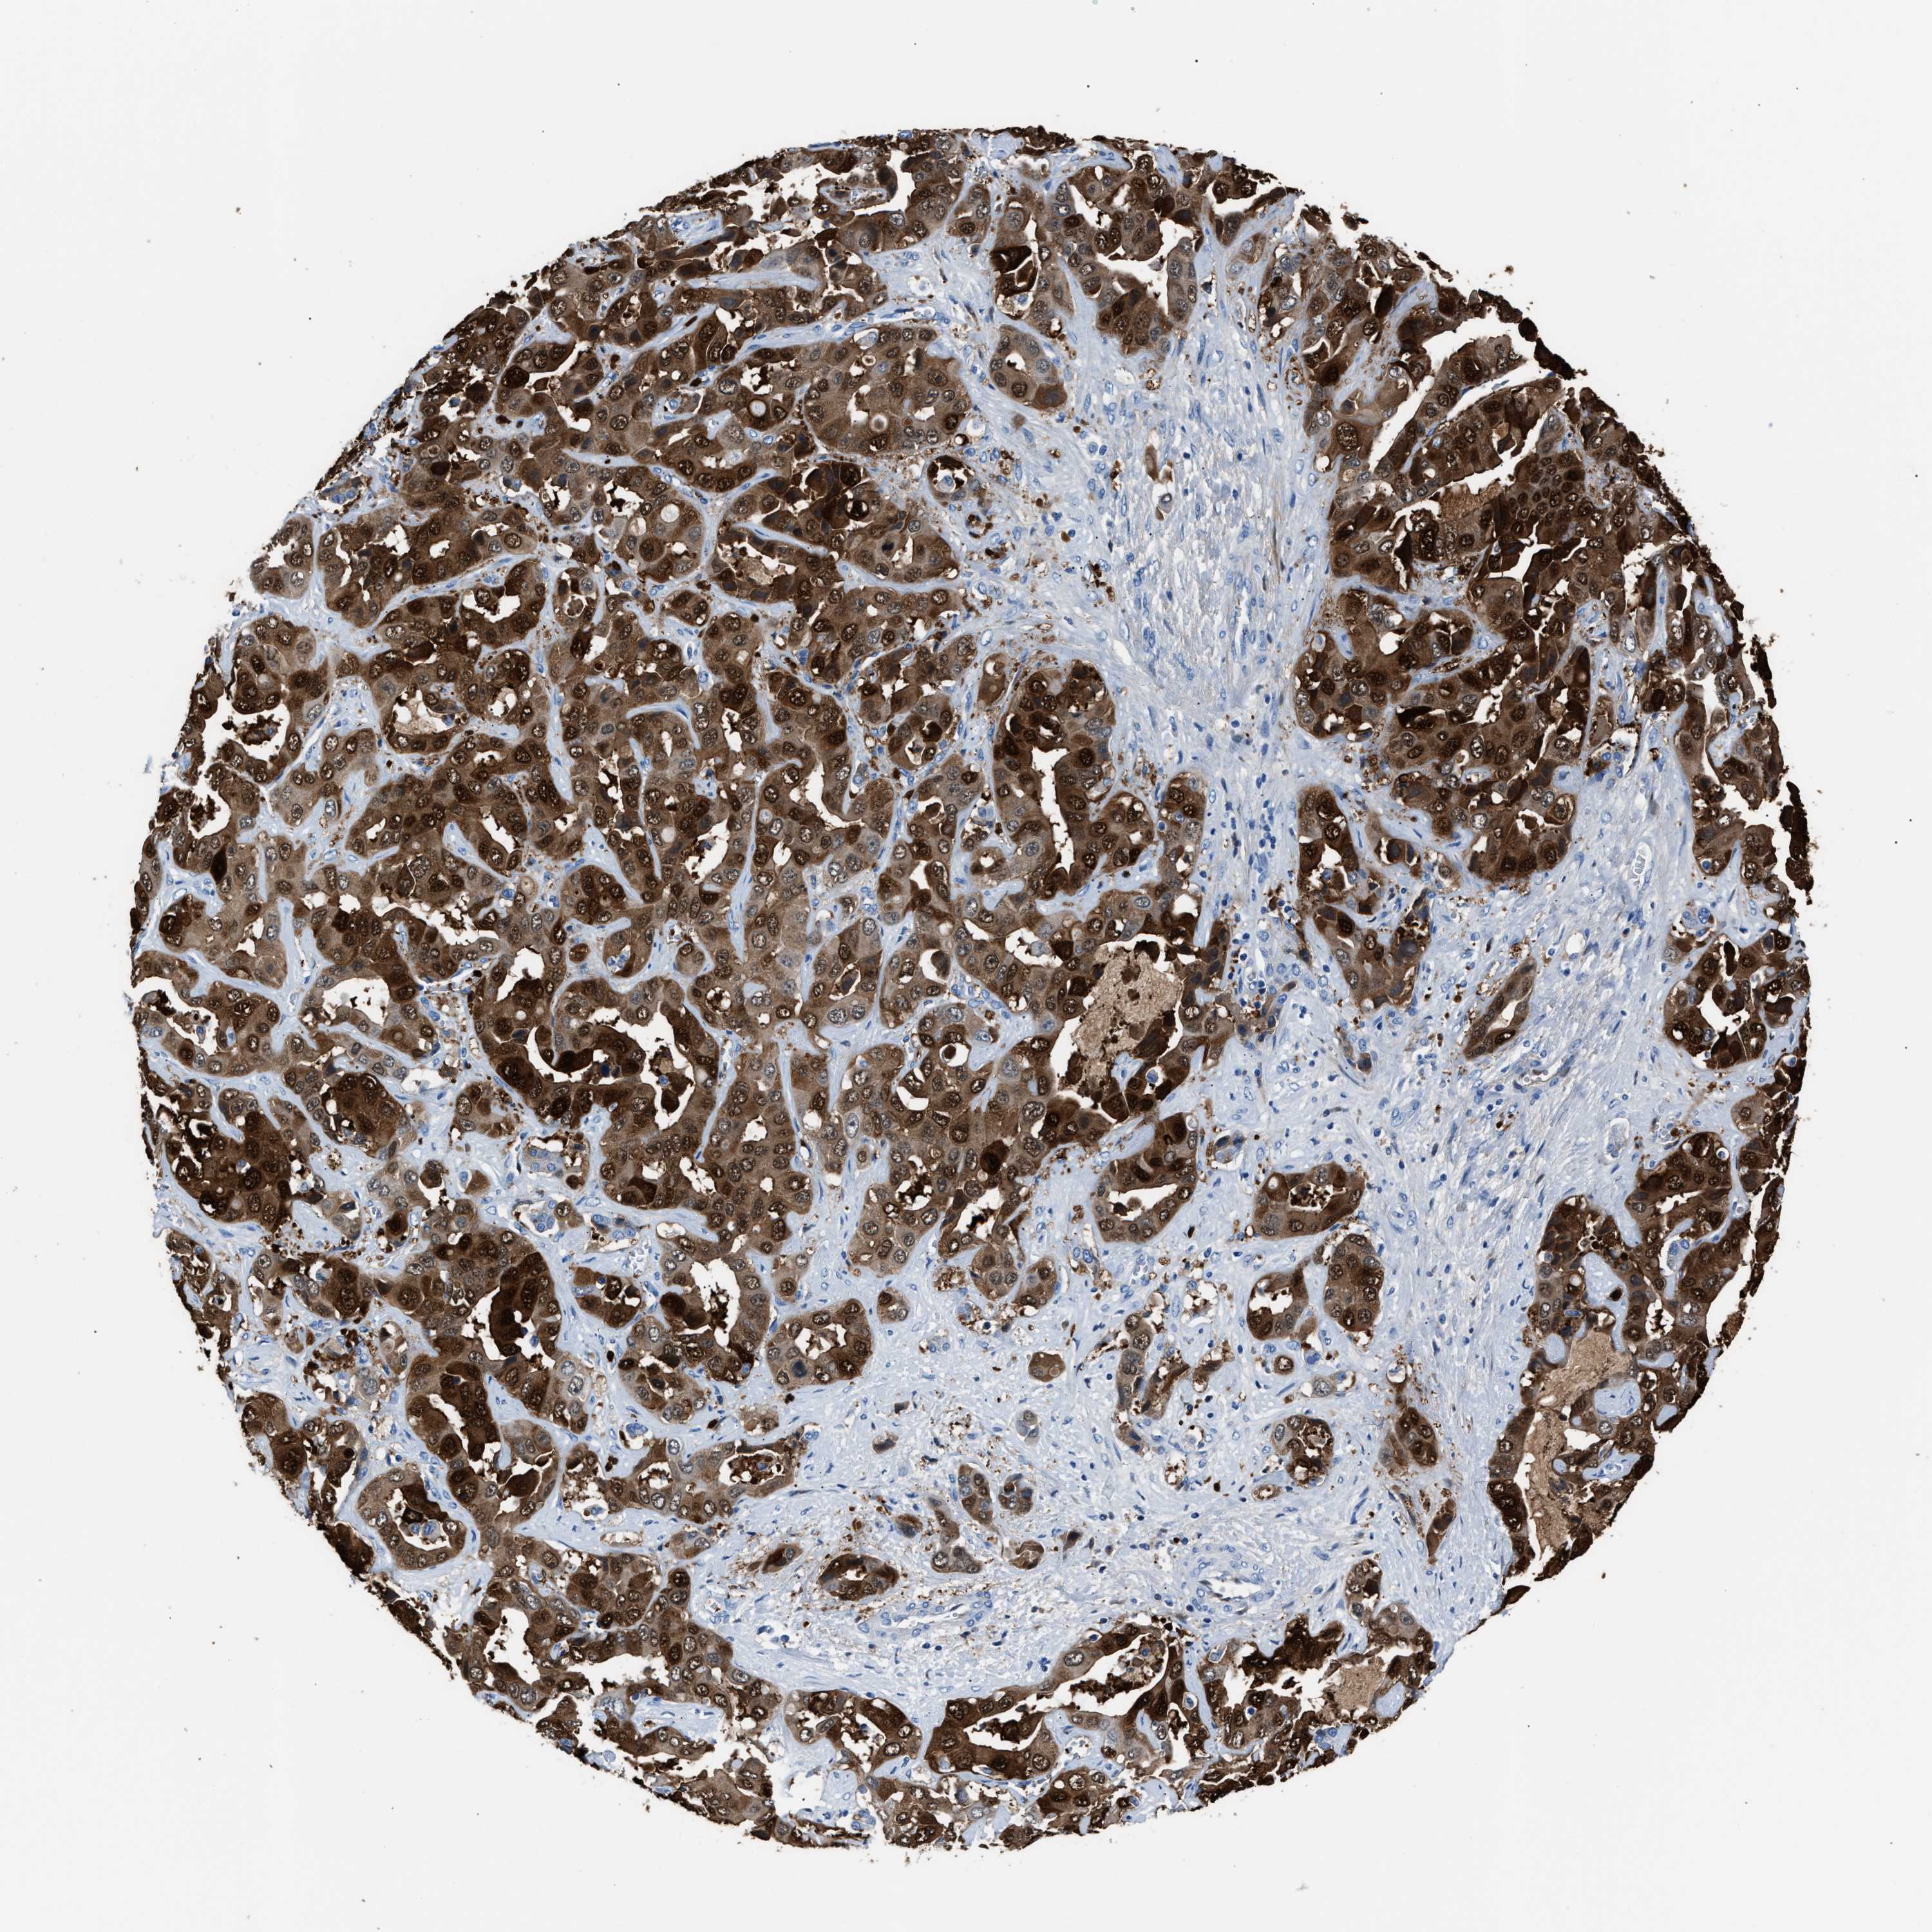

LIVER CANCER - Protein expressioni

A mouse-over function shows sample information and annotation data. Click on an image to view it in a full screen mode. Samples can be filtered based on level of antibody staining by selecting one or several of the following categories: high, medium, low and not detected. The assay and annotation is described here.

Note that samples used for immunohistochemistry by the Human Protein Atlas do not correspond to samples in the TCGA dataset.

Antibody stainingi

Antibody staining in the annotated cell types in the current human tissue is reported as not detected, low, medium, or high, based on conventional immunohistochemistry profiling in selected tissues. This score is based on the combination of the staining intensity and fraction of stained cells.

Each image is clickable and will lead to virtual microscopy that enables deeper exploration of all samples and also displays staining intensity scores, fraction scores and subcellular localization as well as patient and tissue information for each sample.

Antibody HPA019502

Staining

High

Medium

Low

Not detected

Intensity

Strong

Moderate

Weak

Negative

Quantity

>75%

75%-25%

<25%

None

Location

Nuclear

Cytoplasmic/membranous

Cytoplasmic/membranous,nuclear

Cholangiocarcinoma

Carcinoma, Hepatocellular, NOS